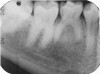

Fig 5. Three thin soft dental picks were used simultaneously for SDF proximal surface saturations in a teenaged patient (Fig 3). After 60 seconds, the treated regions were covered with 5% fluoride varnish (Fig 4). A comparison can be seen of pre-SDF-treatment bitewing films (Fig 5) and 8-month post-SDF bitewing films (Fig 6) for the patient shown in Fig 3 and Fig 4. Radiolucencies were similar or improved, except for contact of maxillary first and second molars.

Fig 6. Three thin soft dental picks were used simultaneously for SDF proximal surface saturations in a teenaged patient (Fig 3). After 60 seconds, the treated regions were covered with 5% fluoride varnish (Fig 4). A comparison can be seen of pre-SDF-treatment bitewing films (Fig 5) and 8-month post-SDF bitewing films (Fig 6) for the patient shown in Fig 3 and Fig 4. Radiolucencies were similar or improved, except for contact of maxillary first and second molars.

Fig 3. Three thin soft dental picks were used simultaneously for SDF proximal surface saturations in a teenaged patient (Fig 3). After 60 seconds, the treated regions were covered with 5% fluoride varnish (Fig 4). A comparison can be seen of pre-SDF-treatment bitewing films (Fig 5) and 8-month post-SDF bitewing films (Fig 6) for the patient shown in Fig 3 and Fig 4. Radiolucencies were similar or improved, except for contact of maxillary first and second molars.